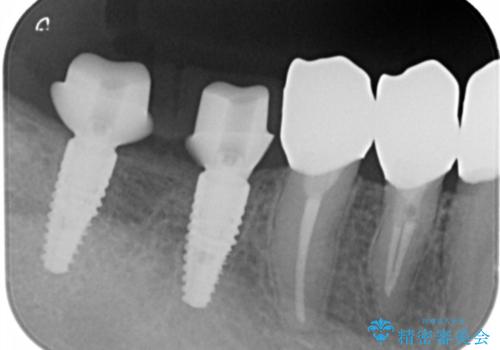

検査の結果、残すことの難しい歯をインプラントに置き換え、残すことのできる歯は虫歯の徹底的な除去後にセラミック治療を行っていくこととしました。

- 125万円(インプラント×2・チタンカスタムアバットメント×2・ジルコニアクラウン×4・仮歯×4)費用は治療当時の料金となります

銀歯が口腔内からなくなり審美的になっただけでなく、歯ブラシのしやすさや噛み合わせの安定、口臭の減少など、良好な結果を得ることができました。